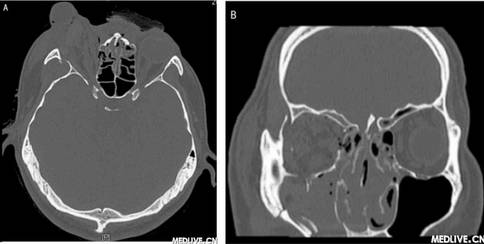

双眶三维CT 右侧眼球外突双眶三维CT 右眼眶下壁骨折

图2 双眶三维CT

A:右眼球外突,考虑存在右眼肌群及视神经损伤。右侧玻璃体内稍高密度影,出血可能性大。双侧上颌窦、筛窦、蝶窦及右侧额窦内积液;

B:右眼眶下壁骨折。